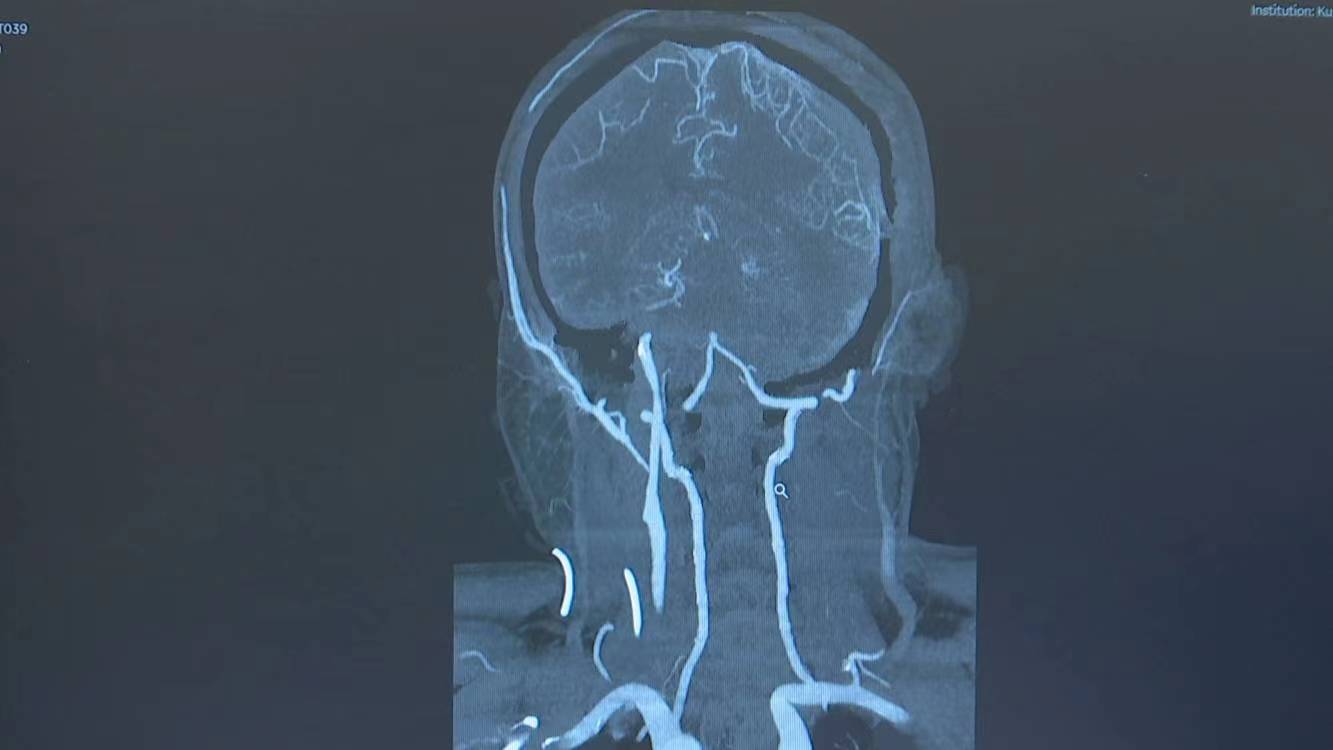

今年8月中旬,48岁的单先生突然感觉自己左侧手脚不太灵便,说话也没有平时利索,在出现意识昏迷后,被120救护车送至市一医院救治。在经过MRI检查后,医生初步诊断为脑梗死。可是单先生平时作息规律,既没有高血压,也没有糖尿病、高血脂等引起脑梗死的危险因素,那到底是什么原因引起的呢?在进一步做了头颈部CT血管造影检查后,单先生被确诊为烟雾病。

烟雾病又称脑底异常血管网病,是一种极其罕见,且原因不明,形成于颅底异常血管网的慢性脑血管疾病。该病在血管造影时会看到一团烟雾似的血管,被形象地称为烟雾病。这些微小的烟雾状血管比正常血管更脆弱,极易破裂出血并流入大脑。